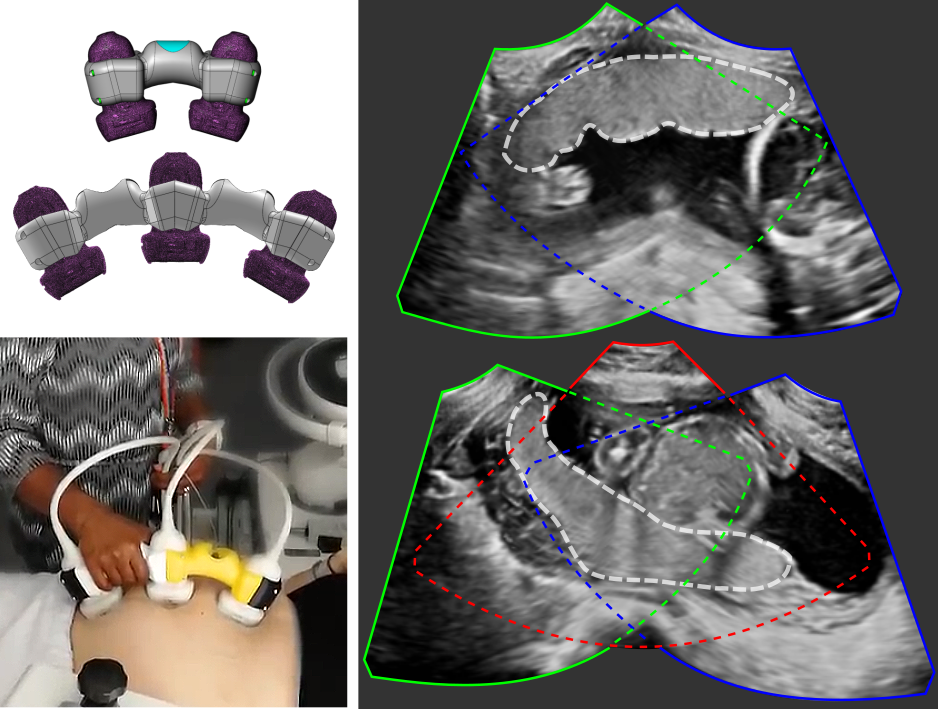

Multi-view placenta imaging with US requires two steps: (i) the image acquisition using multiple probes, and (ii) the multi-view image fusion, see Fig. 1 (b) for illustration.

Multi-probe ultrasound imaging. We acquire multiple US images using an in-house US signal multiplexer which allows to connect multiple Philips X6-1 probes to a Philips EPIQ V7 US system. The multiplexer switches rapidly between up to three probes so that images from each probe are acquired in a time-interleaved fashion. The manual movement speeds of the transducer array is within the Nyquist sampling rates. Therefore, for the purpose of data processing, consecutive images are assumed to have been acquired simultaneously over a small time window.

We designed a physical device that fixes the probes in an angle of 30∘ to each other, which ensures a large overlap between the images (see Fig. 1 (b)), and allows easy and comfortable operation. A.1 with Fig. 10 describe and show a more detailed illustration of the probe holder design with exact measurements.

Examplary multi-view images are shown in Fig. 5 with corresponding placenta segmentations with MTUNet and combined attention maps. The placenta is better visualized in the multi-view images with reduced image artifacts and an extended FoV. The multi-task model MTUNet provides an accurate segmentation and the combined attention maps localize well the placenta. Further examples of multi-view images with corresponding segmentations can be found in Fig. 12 in the appendix.